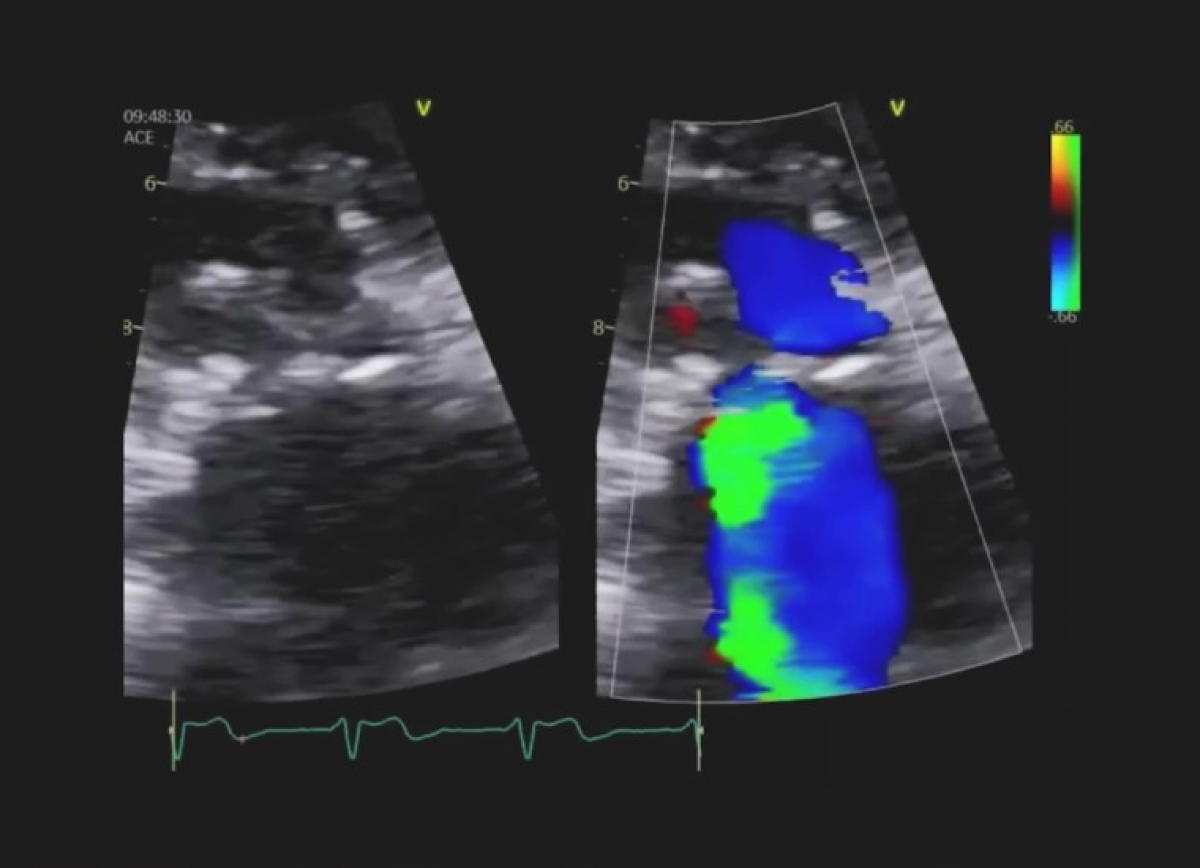

Pacjentka z niewydolnością serca NYHA III, po wymianie zastawki mitralnej, z utrwalonym migotaniem przedsionków, po implantacji kardiostymulatora.

Dysfunkcja bioprotezy mitralnej – niedomykalność wewnątrzzastawkowa.

Echokardiografia przezklatkowa i przezprzełykowa

Echokardiografia trójwymiarowa.

Ocena zastawek biologicznych.